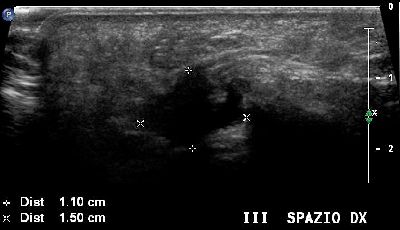

Altro neuroma di Morton del terzo spazio intermetatarsale Neuroma Morton